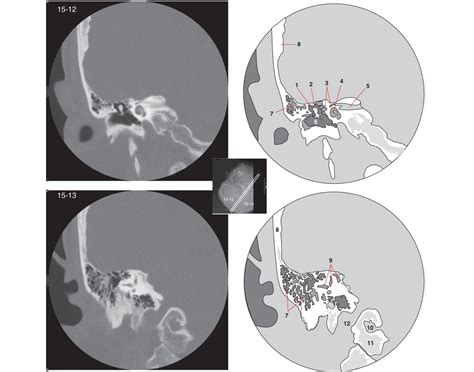

Interpreting Ct Temporal Bone scans requires a keen eye for detail and a thorough understanding of the temporal bone's anatomy. Here are some key points to consider when interpreting these scans:

• Bone Density: Abnormalities in bone density, such as areas of increased or decreased density, can indicate conditions like otosclerosis or infections.

• Fractures: Fractures of the temporal bone can be detected by looking for discontinuities in the bone's structure.

• Erosions: Erosions or destruction of the temporal bone can be seen in conditions like cholesteatoma or mastoiditis.

• Soft Tissue Abnormalities: While CT is primarily used for bony structures, it can also detect soft tissue abnormalities, such as fluid collections or masses.

Radiologists often use a systematic approach to review Ct Temporal Bone scans, starting with the outer ear and progressing inward to the inner ear structures. This ensures that no abnormalities are missed.

Several common findings can be identified in Ct Temporal Bone scans, each with its own clinical significance. Here are some of the most frequently encountered findings:

Finding Description Clinical Significance

Otosclerosis Increased bone density around the oval window Hearing loss

Cholesteatoma Soft tissue mass with bone erosion Potential for hearing loss and facial nerve damage

Mastoiditis Fluid collection and bone erosion in the mastoid air cells Infection and potential for intracranial complications

Facial Nerve Palsy Abnormalities in the facial nerve canal Facial muscle weakness or paralysis